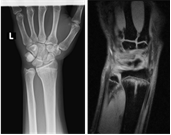

様々な部位や疾患の検査において幅広い診断情報を得るために、当院では整形外科の検査に特化した最新のオープン型MRIを導入しております。

X線一般撮影では判別しづらい骨折や骨のダメージ、靭帯など軟部組織の精査が可能です。

背骨や関節の検査に特化したMRIです。独自開発された患部ごとに対応した高感度専用コイル(体内からの信号を受信するアンテナ)と最新の画像技術により、超電導型にせまる高画質を実現しています。